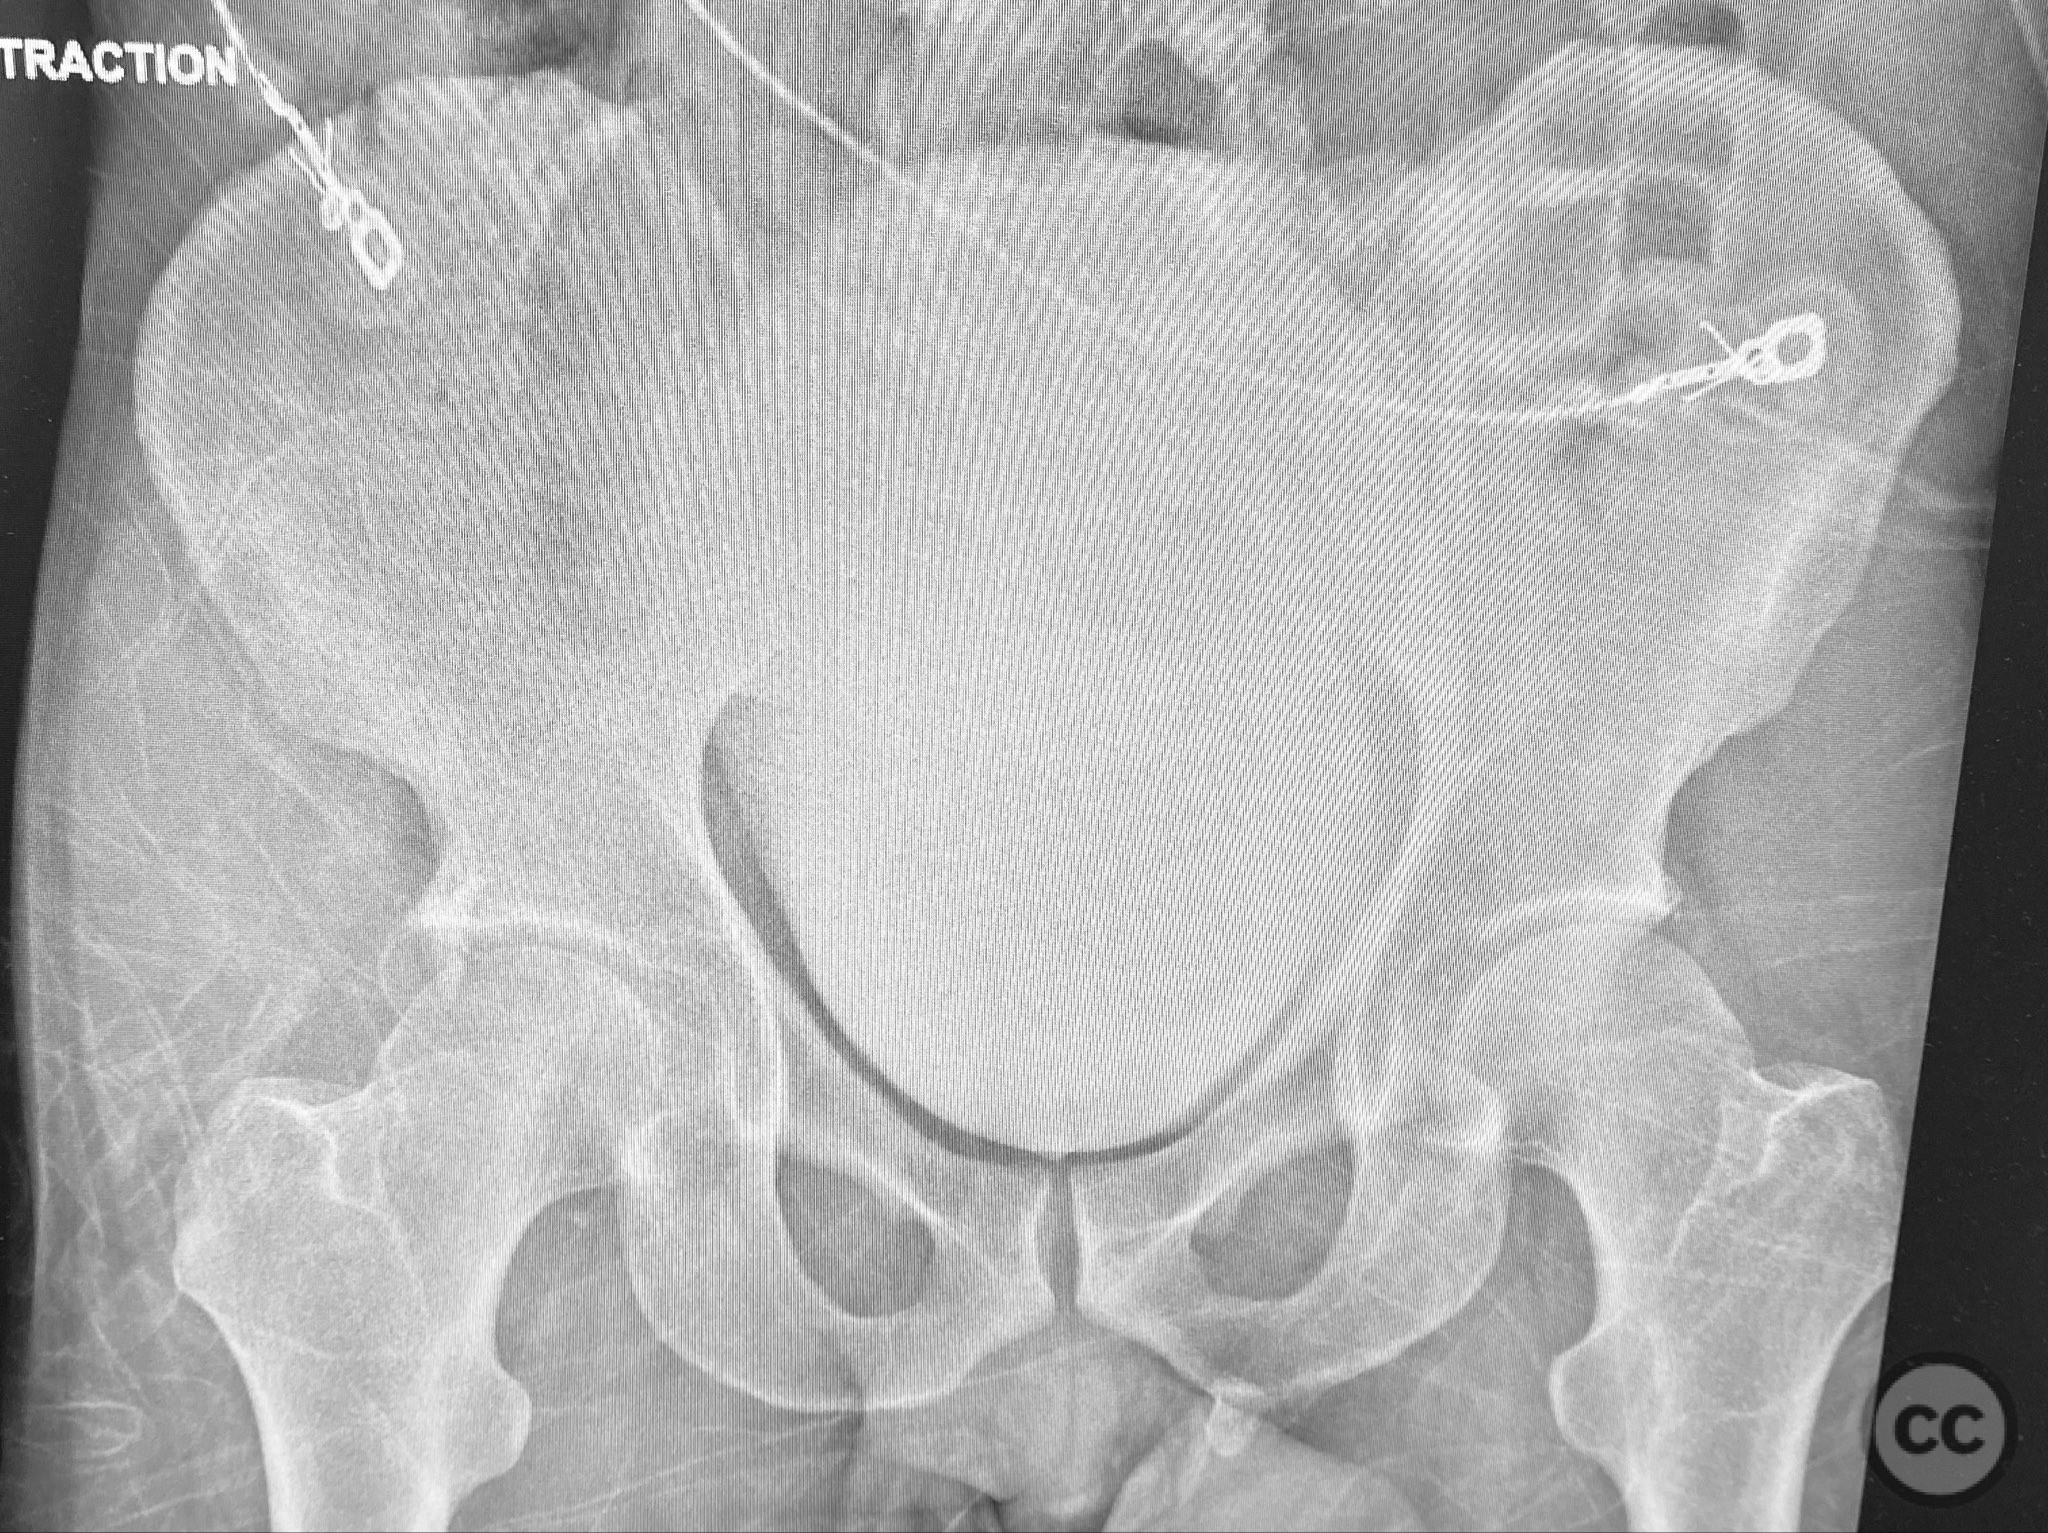

Clinical and radiological findings:  A middle-aged patient sustained a posterior wall acetabular fracture-dislocation, as demonstrated on initial AP pelvic radiograph. The film revealed a sizeable posterior wall fragment, cranial lateral impaction of the acetabular dome, and subtle deformation of the femoral head contour. Neurovascular examination was performed, including assessment of distal pulses and sciatic nerve function. The ipsilateral knee and anterior chest were examined for associated injuries (including possible knee ligamentous injury and thoracic trauma). An initial attempt at closed reduction under sedation was unsuccessful.

Patient positioning:  The patient was positioned prone on a radiolucent table, with all pressure points padded. Skeletal traction was maintained via a distal femoral K-wire and tensioning bow throughout the procedure.